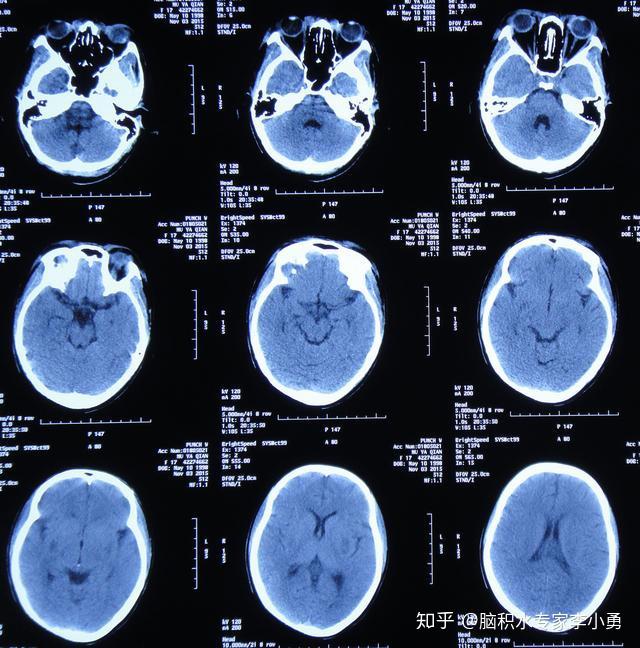

入院头颅ct显示双侧蛛网膜下腔,纵裂,基底池脑室广泛出血